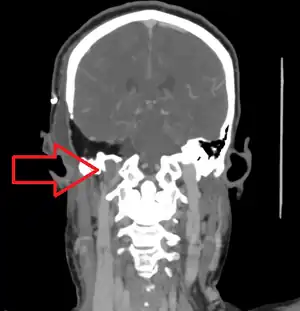

| A post-operative internal jugular vein thrombosis on the person's right | |

| Diagnostic method | Ultrasound, CT scan[1] |

Diagnosis may be suspected based on the D-dimer and confirmed by ultrasound or CT scan.[1]